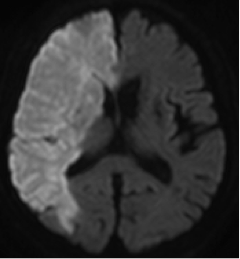

3)心原性脳塞栓症

心房細動、心臓弁膜症、心筋梗塞などの心臓の病気により、心臓内に形成された血栓(血の塊)が流出し、脳の動脈を閉塞することにより起きる脳梗塞です。片麻痺、言語障害など症状が突然出現し、一気に完成するのが特徴です。詰まる血管が太い場合には最初から意識障害が出現し、生命に関わることがあります。3種類の脳梗塞の中で、最も重症になりやすい脳梗塞です。